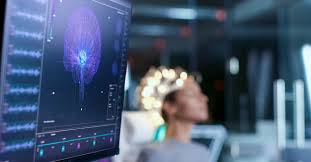

Selon un communiqué publié le même jour, les neurotechnologies offrent des perspectives prometteuses, notamment en médecine, où la stimulation cérébrale profonde atténue les symptômes de troubles comme la dépression ou la maladie de Parkinson, et où les interfaces cerveau-ordinateur permettent à des personnes en situation de handicap de contrôler des prothèses ou de communiquer par la pensée.

Si leur usage médical est strictement encadré, les neurotechnologies restent peu régulées dans d’autres domaines.